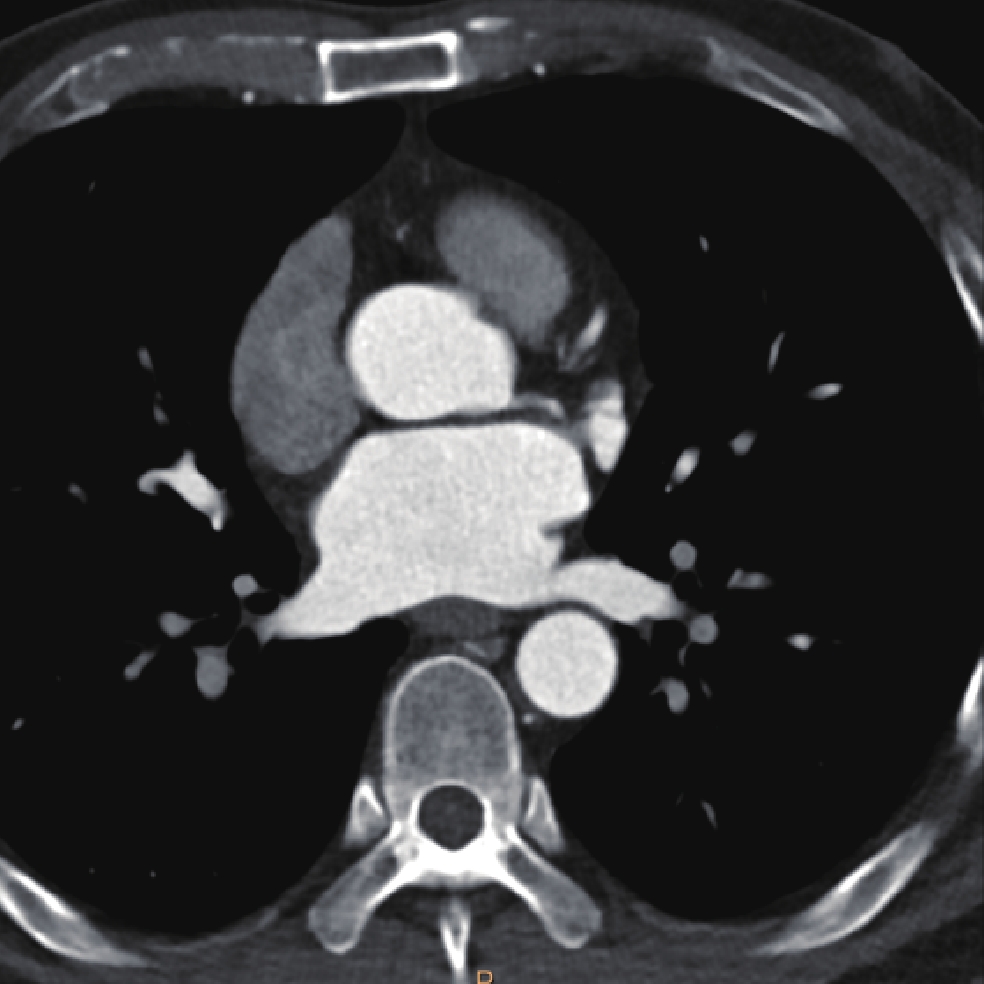

• 摘要: 目的:探讨不同扫描模式对胸主动脉CTA图像质量和辐射剂量的影响。方法:回顾性分析未应用心电门控技术的30例胸主动脉CTA(组1,对照组),使用回顾性心电门控的30例冠脉CTA重建舒张期(组2)和收缩期(组3)时相,30例应用宽曝光脉冲前瞻性心电门控技术(组4)共4组图像的质量和辐射剂量。分别记录、计算4组的图像质量客观指标CT值、噪声、CNR和辐射剂量指标CTDIvol。对图像质量进行四分法主观评价。对主客观指标分别统计分析。结果:客观指标CNR组1与组2、3、4均有差异,组2、3、4间均无差异;主观评分两两比较组2~4显著高于组1,组2~4间无差异。非门控组(组1)、回顾门控组(组2和组3)和前瞻门控组(组4)的CTDIvol分别为13.70(11.87,16.58)、12.62(10.03,15.01)、11.54(8.92,15.56),差异无统计学意义。结论:在胸主动脉CTA中推荐使用窄曝光脉冲的前瞻性心电门控收缩期或舒张期扫描,可显著提高胸主动脉心脏段图像质量并降低辐射剂量。

Abstract: Objective: This study aimed to compare the effects of different scanning modes on image quality and radiation dose in thoracic aortic computed tomography angiography (CTA). Methods: The image quality and radiation dose of 30 cases of thoracic aortic CTA (Group 1, control group), 30 cases of retrospective CTA diastolic phase (Group 2) and systolic phase (Group 3), and 30 cases of wide-exposure pulse prospective electrocardiogram (ECG) (Group 4) were retrospectively analyzed. The CT value, noise, contrast-to-noise ratio (CNR), signal-to-noise ratio (SNR), and radiation dose (volume CT dose index CTDIvol) were recorded and measured. The image quality was evaluated subjectively using the four points method. The subjective and objective indicators were analyzed statistically. Results: No differences were observed in the objective indexes of noise, CNR and SNR among the groups. The subjective score of pairwise comparison of Groups 2~4 was significantly higher than that of Group 1, and no difference was observed among Groups 2~4. The CTDIvol values of the non-gated group (Group 1), retrospective gated groups (Groups 2 and 3), and prospective gated group (Group 4) were 13.70 (11.87,16.58), 12.62 (10.03,15.01), and 11.54 (8.92,15.56), respectively, without a statistically significant difference.